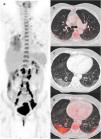

A sample of selected cases, showing a combination of different structural changes and parenchymal lung FDG uptake are illustrated in Figs. 3 and 4.

A 60-year-old woman diagnosed with cervical cancer, PET/CT to evaluate lymph node involvement. The maximum intensity projection image (a) shows increased FDG uptake in the cervix and FDG-avid lymph nodes in the left supraclavicular and infradiaphragmatic locations related to her oncologic pathology. FDG uptake is also visualized in lungs and in hilar and subcarinal lymph nodes, related to infectious/inflammatory pathology. Axial and CT images showed a subpleural band in the right upper lobe (b), peripheral crazy paving pattern in the right lower lobe and bilateral GGO (c) with increased 18F-FDG uptake with SUVmax value of 5.5 (d). The rRT-PCR was positive for COVID-19 (CO-RADS 6).